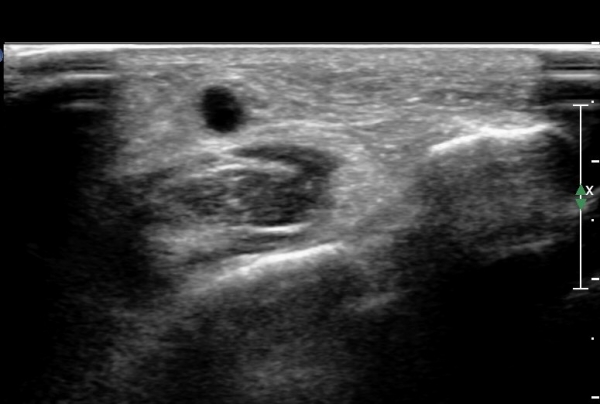

¾ÕÂÊ ¸»´Ü °æ°ñºñ°ñ°üÀý ¾à 5cm ±ÙÀ§ºÎ Ⱦ´Ü몀°Ë»ç ½Ã õºñ°ñ½Å°æ Àü¸é¿¡ Àú¿¡ÄÚ ³¶Á¾¿¡ ÀÇÇÑ ½Å°æ ¾Ð¹ÚÀÌ °üÂûµÈ´Ù(ÀÌ °üÂûµÈ´Ù(»çÁø 6, 7).

¸»´ÜÀ¸·Î °¥ ¼ö ·Ï ³¶Á¾ÀÌ Ä¿Áø°í õºñ°ñ½Å°æ ¾Ð¹ÚÀº ½ÉÇØÁø´Ù(»çÁø 8).